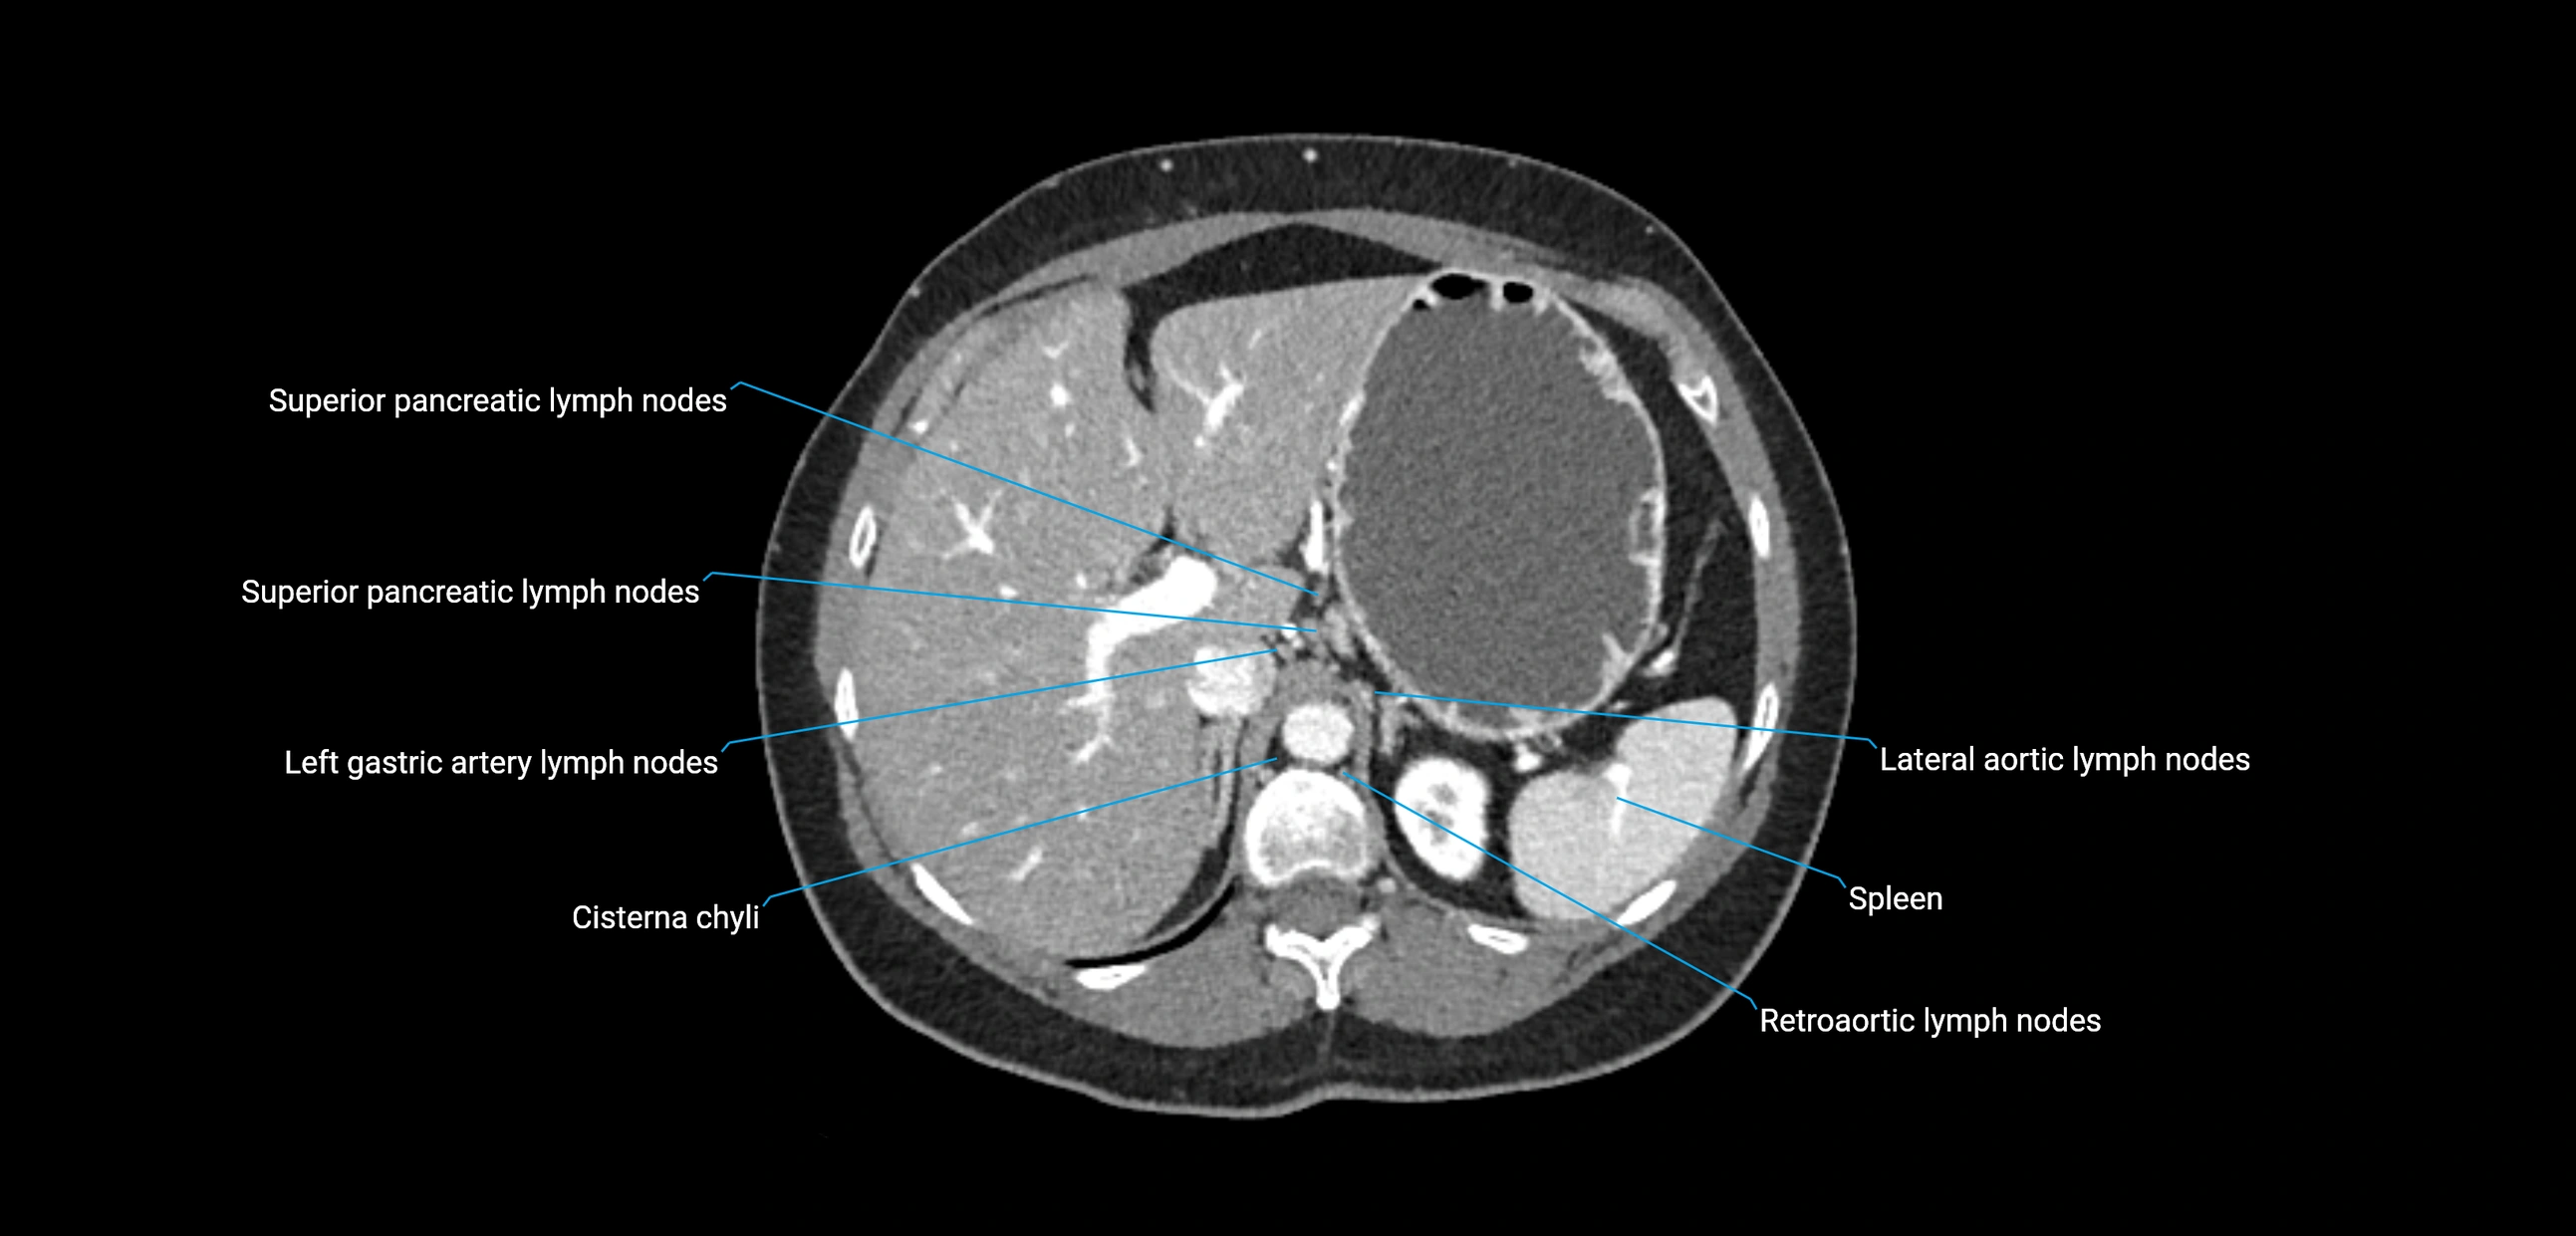

CT Appearance

CT Pre-Contrast:

• Nodes appear as soft-tissue density nodules adjacent to the aorta and IVC

• Calcification may be seen in chronic infections (e.g., tuberculosis)

CT Post-Contrast:

• Normal nodes enhance homogeneously

• Malignant nodes may show heterogeneous enhancement, central necrosis, or conglomerate formation

• Size >1 cm short axis is suspicious, though morphology and distribution are equally important

The lateral aortic lymph nodes (also called para-aortic lymph nodes) are a major group of retroperitoneal lymph nodes located along the abdominal aorta and its branches. They lie between the diaphragmatic crura superiorly and the bifurcation of the aorta at L4 inferiorly.

These nodes receive lymph from a wide range of abdominal and pelvic structures. Specifically, they drain lymph from the kidneys, suprarenal glands, gonads (testes/ovaries), uterus, uterine tubes, and pelvic organs, before converging into the lumbar lymphatic trunks, which terminate in the cisterna chyli → thoracic duct.

Clinically, the lateral aortic lymph nodes are critically important in oncology, being involved in the spread of testicular cancer, ovarian cancer, endometrial cancer, cervical cancer, renal malignancies, and retroperitoneal lymphomas. They are also key targets in retroperitoneal lymph node dissection (RPLND) for testicular tumors.